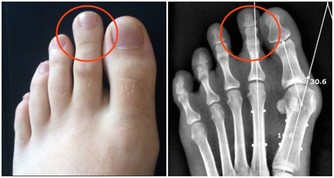

7、潰瘍

人體是非常智慧的為了保護身體,因此在發炎的地方爛掉也不會讓病原菌到處跑。

這時原材料不足的話,身體將潰瘍部位纖維化進入第八步。